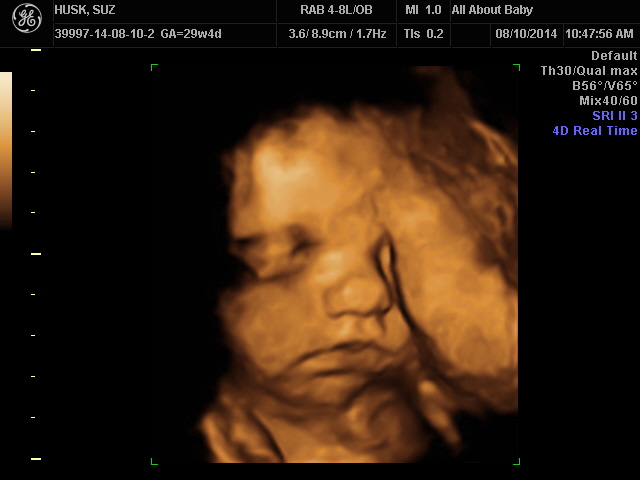

Today: I have an appt this morning that I am super nervous about for no apparent reason. 30 weeks! Time is flying by! I got a bunch of baby stuff done this weekend but my house is a disaster. I need to clean today but I kind of like my bed...

I'm sleepy. still. I slept great last night, but it is never enough.... But I'm feeling fabulous. Yesterday I got to see my little Nemo girl!